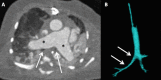

Congenital pulmonary artery anomalies represent a diverse group of abnormalities, ranging from asymptomatic incidental findings to causes of sudden cardiac death. While some may be recognized in childhood, others may be found incidentally in adulthood. We review the clinical and imaging findings in patients with congenital anomalies of the pulmonary arteries, including valvular and perivavular anomalies as well as abnormal narrowing, course and communications of the pulmonary arteries. We also discuss the role of various imaging modalities in the evaluation of these patients. It is vital to be aware of the key radiologic manifestations and associated haemodynamic consequences in these conditions in order to facilitate accurate diagnosis and prognostic stratification.